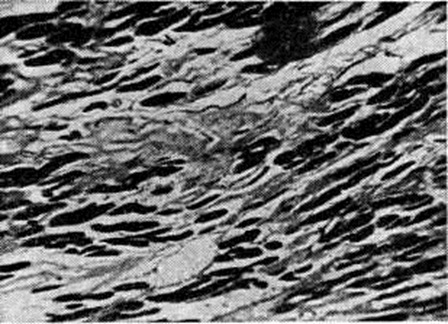

Миокардитический кардиосклероз — исход миокардитов (смотри полный свод знаний) инфекционно-аллергической, бактериальной или вирусной этиологии, сопровождающихся экссудативными и пролиферативными процессами в строме миокарда и деструктивными изменениями миоцитов. К этим процессам относится Кардиосклероз после перенесённого ревматизма, дифтерии, скарлатины, заражения Коксаки-вирусом или энцефаломиокардитическим вирусом, изредка вирусом полиомиелита или оспенной вакцинации; чрезвычайной редкостью является Кардиосклероз после туберкулёзного или сифилитического интерстициального миокардита. Миокардитический Кардиосклероз может носить характер диффузного миофиброза, локализующегося преимущественно в левом желудочке, и выражается в распространённом огрубении аргирофильной стромы миокарда и образовании коллагеновых волокон, что придаёт строме вид грубой решётки, в ячейках которой заключены отдельные мышечные волокна или группы их. Такой Кардиосклероз называют стромогенным. В случае же гибели небольших групп миоцитов возникают небольшие рубчики, или очажки Кардиосклероз. При диффузном ревматическом интерстициальном миокардите с мукоидной дезорганизацией стромы наблюдается диффузный интерстициальный миофиброз (цветной таблица, ст. 144, рисунок 3) и одновременно как исход ревматических гранулем около сосудов возникают овальные или звездчатые рубчики, являющиеся важным диагностическим признаком ревматизма (рисунок 2). Кардиосклероз (диффузный миофиброз) наблюдается также после аллергических миокардитов неясной этиологии (миокардита Фидлера, аллергического миокардита, описанного Я. Л. Рапопортом).

Кардиосклероз как следствие кардиомиопатий в большинстве своём неясной этиологии, развивается при болезни Фредерика, группе мышечных дистрофий, болезни накопления гликогена, гаргоилизме, семейной идиопатической болезни сердца, кардиомиопатии неясной этиологии ненаследственного характера (несемейная идиопатическая гипертрофия миокарда, застойная и гипертрофическая обструктивная кардиомиопатия, идиопатический эндомиофиброз и кардиомегалия жителей. Южной Африки), а также при кардиомиопатиях, связанных с недостатком тиамина и хронический отравлением кобальтом. В этих случаях Кардиосклероз носит характер диффузного миофиброза, иногда называемого заместительным миофиброзом: фиброзной тканью замещаются дистрофически изменённые, атрофирующиеся и гибнущие мышечные волокна (рисунок 3).